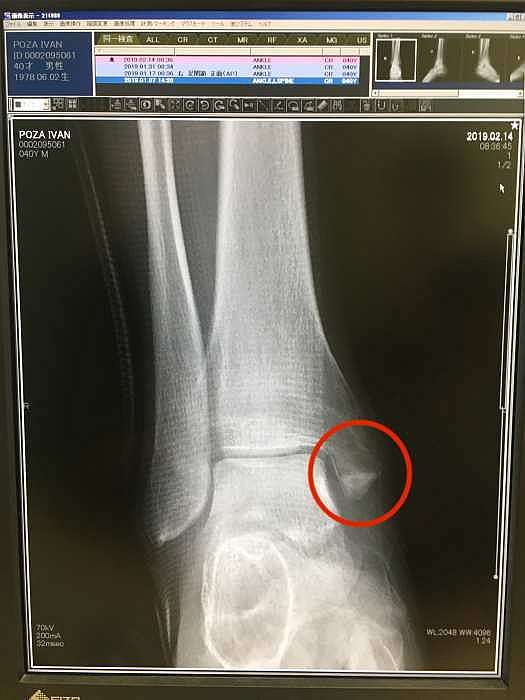

- 4 Radiografías de articulación de pie derecho (migi ashi kansetsu 右足関節): 3.350 yenes

Bueno, volviendo al tema de la lesión, deciros que comencé la rehabilitación en la quinta semana y media, después de que se viera en la radiografía que la fractura estaba consolidando bien.